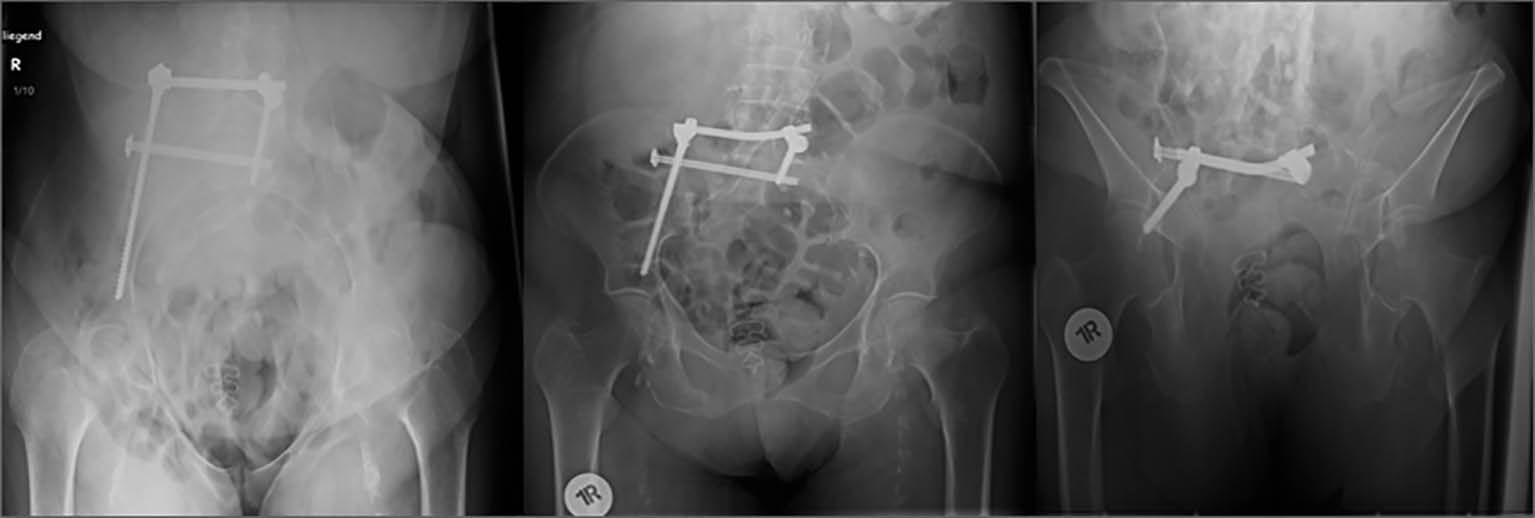

Abb. 3: postoperative konventionell radiologische Kontrolle nach percutaner horizontaler Stabilisierung des hinteren Beckenrings rechts mit Fixateur interne und iliosacraler Schraube („iliosacrales bridging“) in inlet-, anterior-posteriorer und outlet-Projektion

In der Folge wurden auch Ergebnisse nach Zementaugmentation dieser Fixateuranordnung bei instabilen Fragilitätsfrakturen beschrieben [18]. Es besteht als Modifikation dieser Methode zudem die Möglichkeit, den horizontalen Fixateur zur Versorgung unilateraler Becken-B-Verletzungen einzusetzen. Dies gelingt durch eine Verkürzung der Fixateuranordnung und Platzierung einer Schraube auf der unverletzten Seite des Os sacrum in Höhe des S1-Pedikels. Über das Instrumentarium des Fixateurs besteht zusätzlich die Möglichkeit einer gewissen Kompression im Frakturbereich. Zudem kann sowohl mono- als auch bilateral durch eine ergänzende transiliosakrale Verschraubung („iliosacrales bridging“) [Abb. 3 und 4] die Stabilität weiter erhöht werden [17], wobei durch die horizontal hintereinander liegenden Implantate (iliosacrale Schraube + Fixateurquerträger) die Stabilität gegenüber den weiteren beschriebenen Verfahren nochmals deutlich erhöht sein müsste. Bei relativ neuer Osteosynthesetechnik stehen hierzu jedoch vergleichende Studien noch aus. Das „iliosacrale bridging“ zeigt bei einem von Altersstruktur und Verletzungsschweren gemischten Patientenkollektiv gute Ergebnisse.